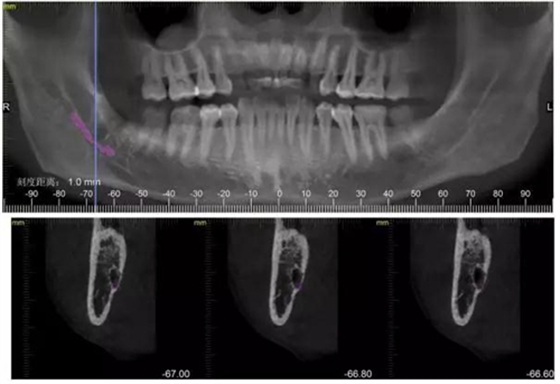

下面CBCT,可以看到兩個牙根的根尖三分之一在神經(jīng)管里面。

CBCT神經(jīng)管標(biāo)線,可以看到標(biāo)線不能連續(xù),中間被阻斷。